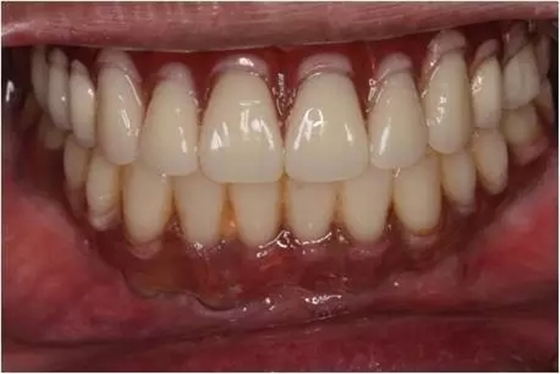

患者男性,51歲,全口無牙,下頜骨量尚可,上頜后牙區(qū)上頜竇底剩余骨高度嚴(yán)重不足,前牙區(qū)牙槽突較豐滿,主訴希望全口種植固定義齒修復(fù)。于2015年 9月接受種植治療:上頜采用All-on-4種植方案、下頜采用常規(guī)種植6顆種植體方案,種植后行即刻修復(fù)(圖1-2)。

1、在25區(qū)補種1顆傾斜種植體,恢復(fù)ALL-on-4修復(fù)方案。造成之前種植體失敗的原因與其受力有關(guān),可能來自于修復(fù)體的咬合設(shè)計,也可能源于上、下頜種植體數(shù)量上的差異(通常上頜種植體數(shù)量應(yīng)多于下頜)。另外,放射學(xué)檢查顯示,15區(qū)種植體邊緣骨吸收較明顯,也提示存在支撐力不足的問題。后來追問病史,該患者修復(fù)后有夜磨牙情況,這進一步證實了上述判斷。鑒于此,這個方案暫不做考慮。2、增加上頜種植體數(shù)量,分別與16、25、26植入3顆,行6顆種植體支撐的常規(guī)種植固定義齒修復(fù)(圖7)。16、25、26區(qū)剩余骨高度嚴(yán)重不足是該方案的不利方面,存在因需要上頜竇底提升手術(shù)所帶來的相應(yīng)手術(shù)風(fēng)險。但是,上頜竇底提升術(shù)是一個成熟、可靠的技術(shù)方法,經(jīng)過與患者充分溝通,最終選擇了這一方案。

1、開窗法雙側(cè)上頜竇底提升術(shù),聯(lián)合25區(qū)植骨術(shù);2、6個月后延期種植,分別與16、25、26植入3顆種植體(如圖7所示);為什么選擇開窗法上頜竇底提升延期種植手術(shù)方案?上頜竇底提升同期種植的標(biāo)準(zhǔn)是植入種植體能夠獲得初期穩(wěn)定性,竇底植骨材料不具有增加種植體穩(wěn)定性的作用,共識性意見認(rèn)為剩余骨高度一般應(yīng)大于4-5mm。開窗法是骨高度嚴(yán)重不足進行上頜竇底提升的有效和可靠術(shù)式。當(dāng)然,國際上也有關(guān)于采用沖壓法提升剩余骨高度僅有1-2mm上頜竇底的成功病例報道,但是目前尚缺乏大樣本、多中心重復(fù)性的臨床研究證明,還沒有得到廣泛的國際共識,不易作為常規(guī)術(shù)式,有待未來進一步的研究。為什么有越來越多種植體掉入上頜竇內(nèi)的病例發(fā)生?這是一個應(yīng)該盡量杜絕的并發(fā)癥,即使臨床發(fā)生率并不高。盲目擴大同期種植適應(yīng)證、種植體無初期穩(wěn)定性是其主要原因。北一種植老師總結(jié):無論種植技術(shù)如何發(fā)展,如何進步。作為一名種植醫(yī)生掌握上頜竇外提升手術(shù)及內(nèi)提升手術(shù)是一項基本功。 因此需要所有醫(yī)生熟練掌握,應(yīng)對各種并發(fā)癥大有幫助。